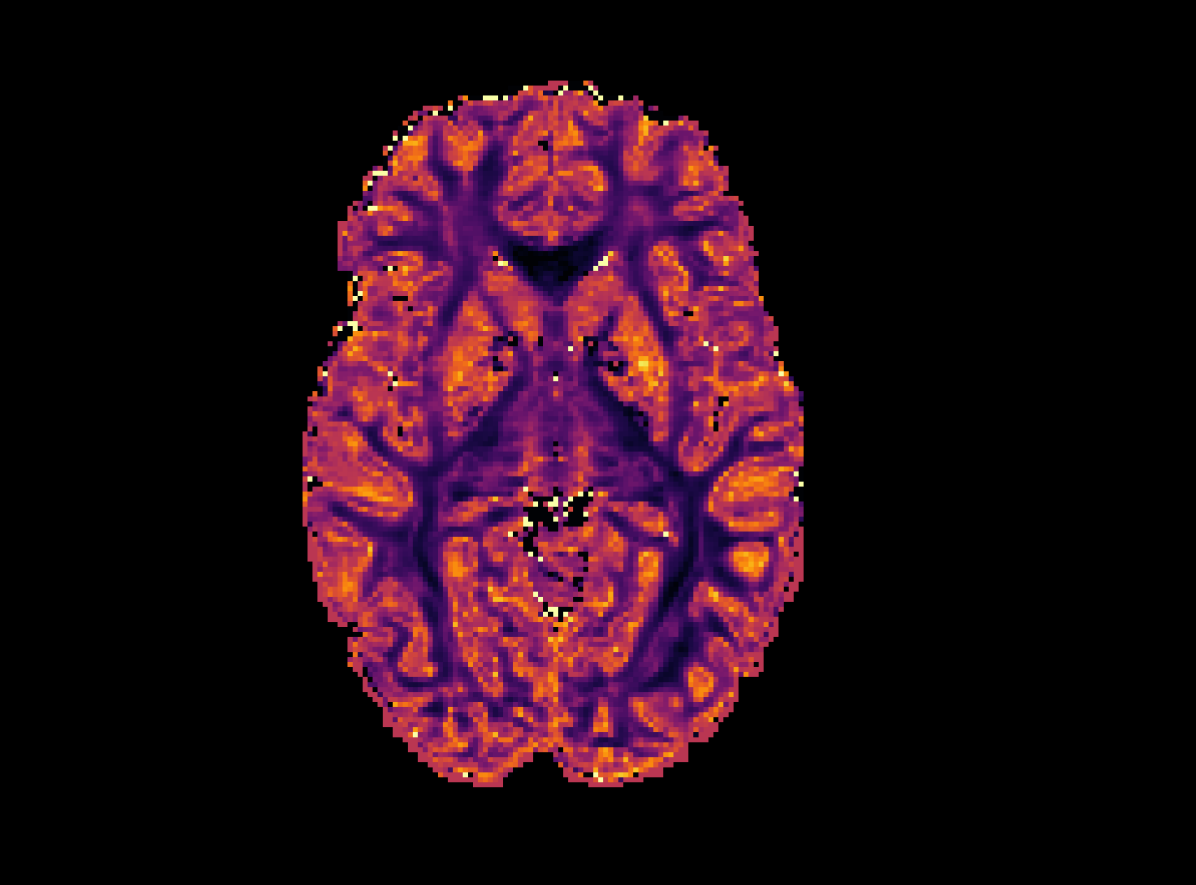

Refer to caption

(a) High Resolution

(b) SR-q-DL

(c) RCNN

Refer to captionRefer to caption

(d) PCCNN-Bv

Figure 4: Axial slice of orientation dispersion index (OD) within one subject across different models. Models use single-shell data (b=1000s/mm2𝑏1000ssuperscriptmm2b=1000\mathrm{s/mm^{2}}) with angular dimension size qin=10subscript𝑞in10q_{\mathrm{in}}=10 as input, and produce 808080 b=1000s/mm2𝑏1000ssuperscriptmm2b=1000\mathrm{s/mm^{2}}, 909090 b=2000s/mm2𝑏2000ssuperscriptmm2b=2000\mathrm{s/mm^{2}}, and 909090 b=3000s/mm2𝑏3000ssuperscriptmm2b=3000\mathrm{s/mm^{2}} inferred volumes.